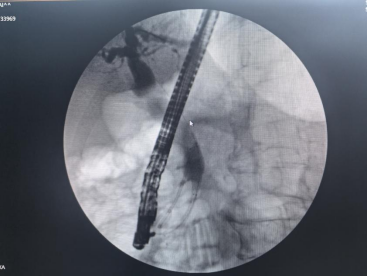

在吴文广教授的指导下,团队成功为一名56岁的胰腺癌患者实施了ERCP手术。检查提示“胰腺头颈部恶性肿瘤伴肝内外胆管及胰腺体尾部主胰管扩张”,针对患者病情,吴文广教授带领团队在术前展开充分讨论,制订了缜密的治疗方案,在与患者及家属充分沟通后最终决定通过内镜下放置胆管支架、胰管支架,为患者解除梗阻。术中,在吴文广教授的指导下,杨晨组长带领团队经预切开、插管、造影、支架置入等一系列操作,团队成功解除了胆道梗阻,最终成功引流出黑色胆汁,手术取得成功。